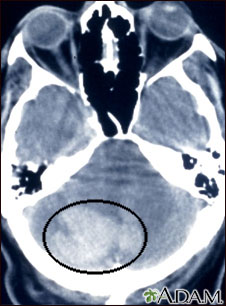

Esta tomografía craneal muestra una hemorragia intracerebelar.